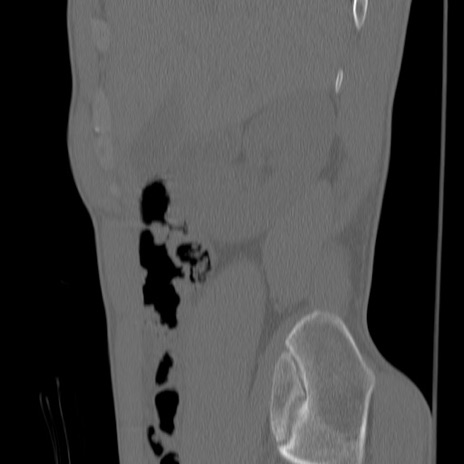

症例3 腰椎CT(矢状断像)

腰椎CT